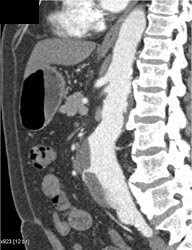

Diagnosis

Av Fistulae